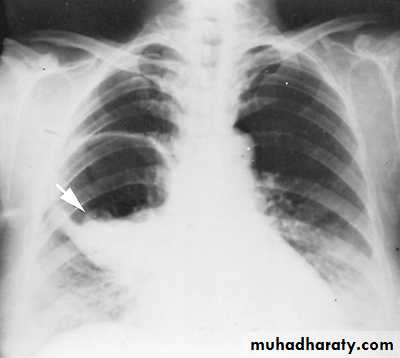

Pleural effusionX-ray of pleural effusion

Massive right effusion